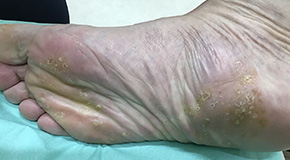

水虫は白癬菌による皮膚の感染症で、頭部や股部、爪など皮膚ならどこにでも感染しますが、一番多いのは足水虫です。水虫は、一度治ったように見えても何度も繰り返すことのある病気です。

水虫では、皮膚がめくれてきたり、水ぶくれができたり、かゆくなったりしますが、他の病気でも同じような症状が出ることがあります。水虫と間違って他の病気に市販の水虫の薬を使ってしまうと、その病気が悪化してしまうこともあり、医療機関で、直接検鏡(白癬菌がいるかどうかを顕微鏡で検査すること)が最も重要です。